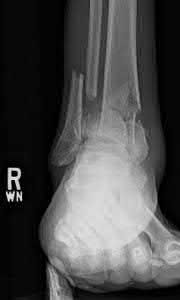

A 64-year-old woman is thrown off a horse, sustaining the injury shown in Figures A and B. She undergoes surgical fixation as seen in Figures C through E. What is the most commonly reported complication of this procedure?

The patient in the scenario has a 2-part proximal humerus fracture treated with a locking plate as seen in Figures A-E. The most common complication with the use of this implant is screw penetration. The terms screw cut out and penetration are often used interchangeably in the literature with cut out appearing more frequently in reports regarding intertrochanteric fractures.

Owsley et al retrospectively reviewed 53 proximal humerus fractures treated with locking plates and the same post-operative protocol. The most common complication was screw cut out or penetration, followed by varus displacement. They concluded that 3 and 4-part fractures in patients over 60 years have a higher incidence of failure.

Agudelo et al retrospectively reviewed 153 patients at a level-one trauma center treated with proximal humerus locking plates, investigating modes of failure for the implant. They determined that varus malreduction (head-shaft angle